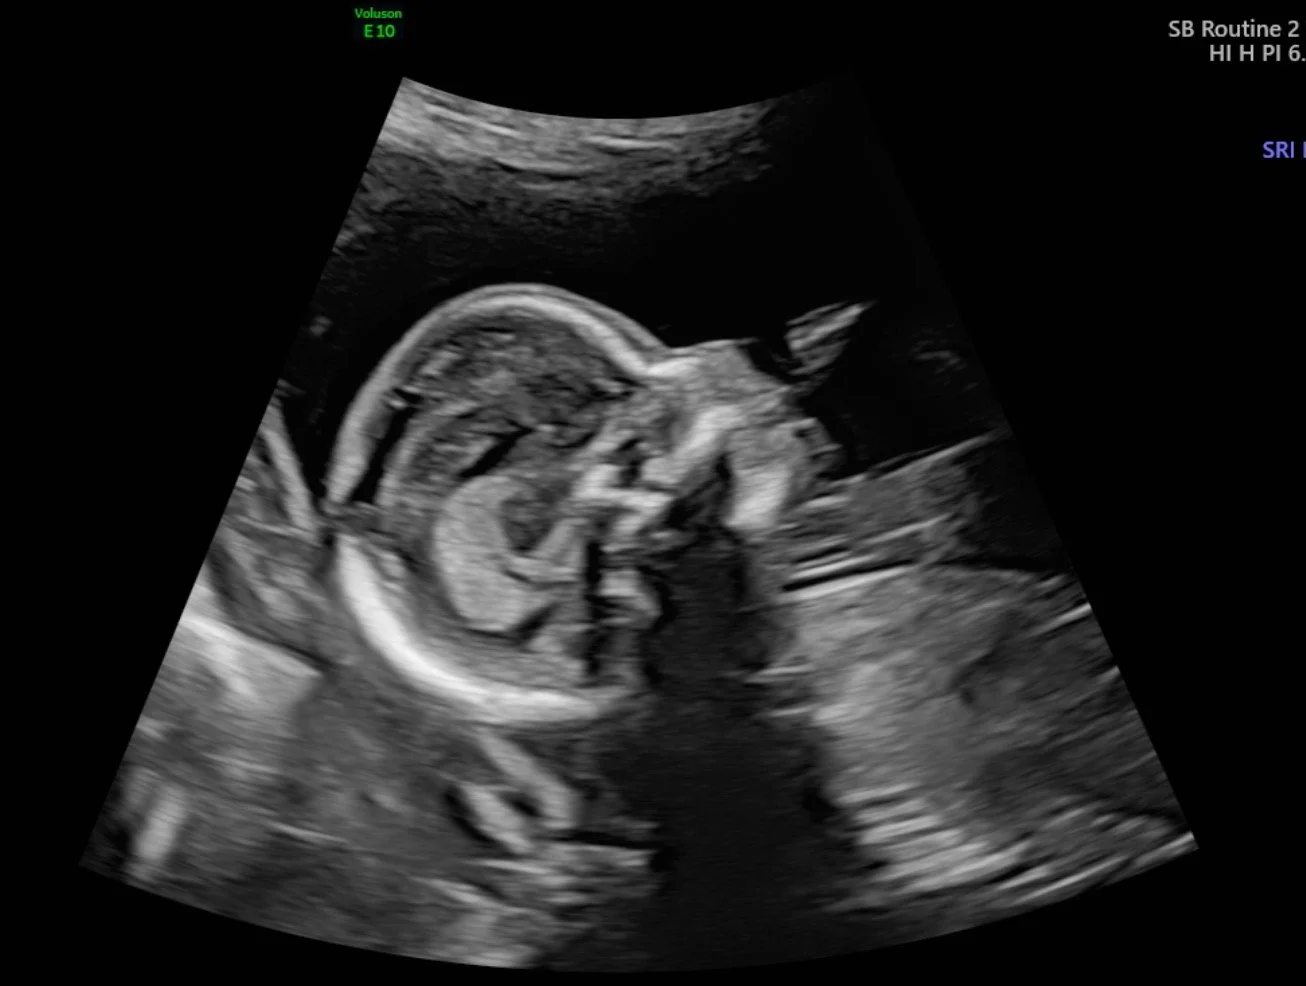

My ultrasound at Mount Sinai Hospital — it was on a large screen above me, and I got to watch everything being done. My doctor was exceptionally thorough and explained everything. Look at our little sweetie!